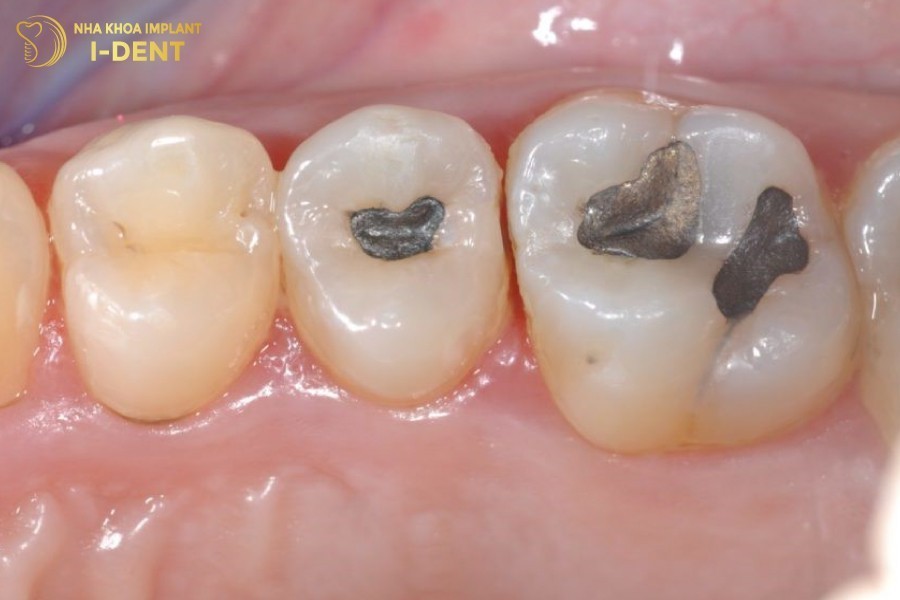

Vết trám răng sai kỹ thuật bị sần sùi và kênh cộm, gây dắt thức ăn khiến việc vệ sinh răng miệng khó khăn. Đây chính là ổ bệnh lớn nhất gây sâu răng trở lại.

Miếng trám kênh cộm, gây dắt thức ăn và dẫn tới sâu răng